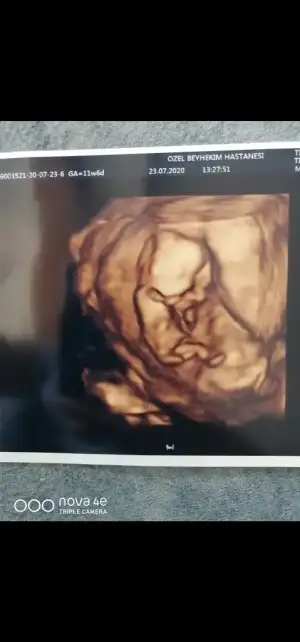

Merhaba ikra meyra benim bebişim içinde tahminde bulunurmusun rica etsem

• IMG_20200728_124139.webp

IMG_20200728_124139.webp

48,6 KB · Görüntüleme: 72

Merhaba, ben kız diye düşündüm ama sizce nedir?